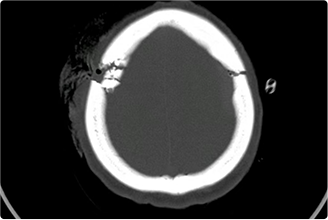

精通颅内动脉瘤介入栓塞和手术夹闭双技术,系统掌握脑动静脉畸形、颈内动脉海绵窦漏、硬脑膜动静脉漏等颅内血管疾病的诊疗和手术,精通颈动脉、椎动脉狭窄的血管内重建技术,以及颈动脉狭窄的内膜剥脱手术技术。在颅内肿瘤、椎管内肿瘤、颅脑损伤、高血压脑出血等疾病的诊治和手术,脑功能性疾病立体定向手术治疗等方面也积累了丰富的经验。

擅长脑血管病(出血与缺血)的神经介入与微创手术,能熟练开展脑外伤、重度颅脑损伤的救治工作。